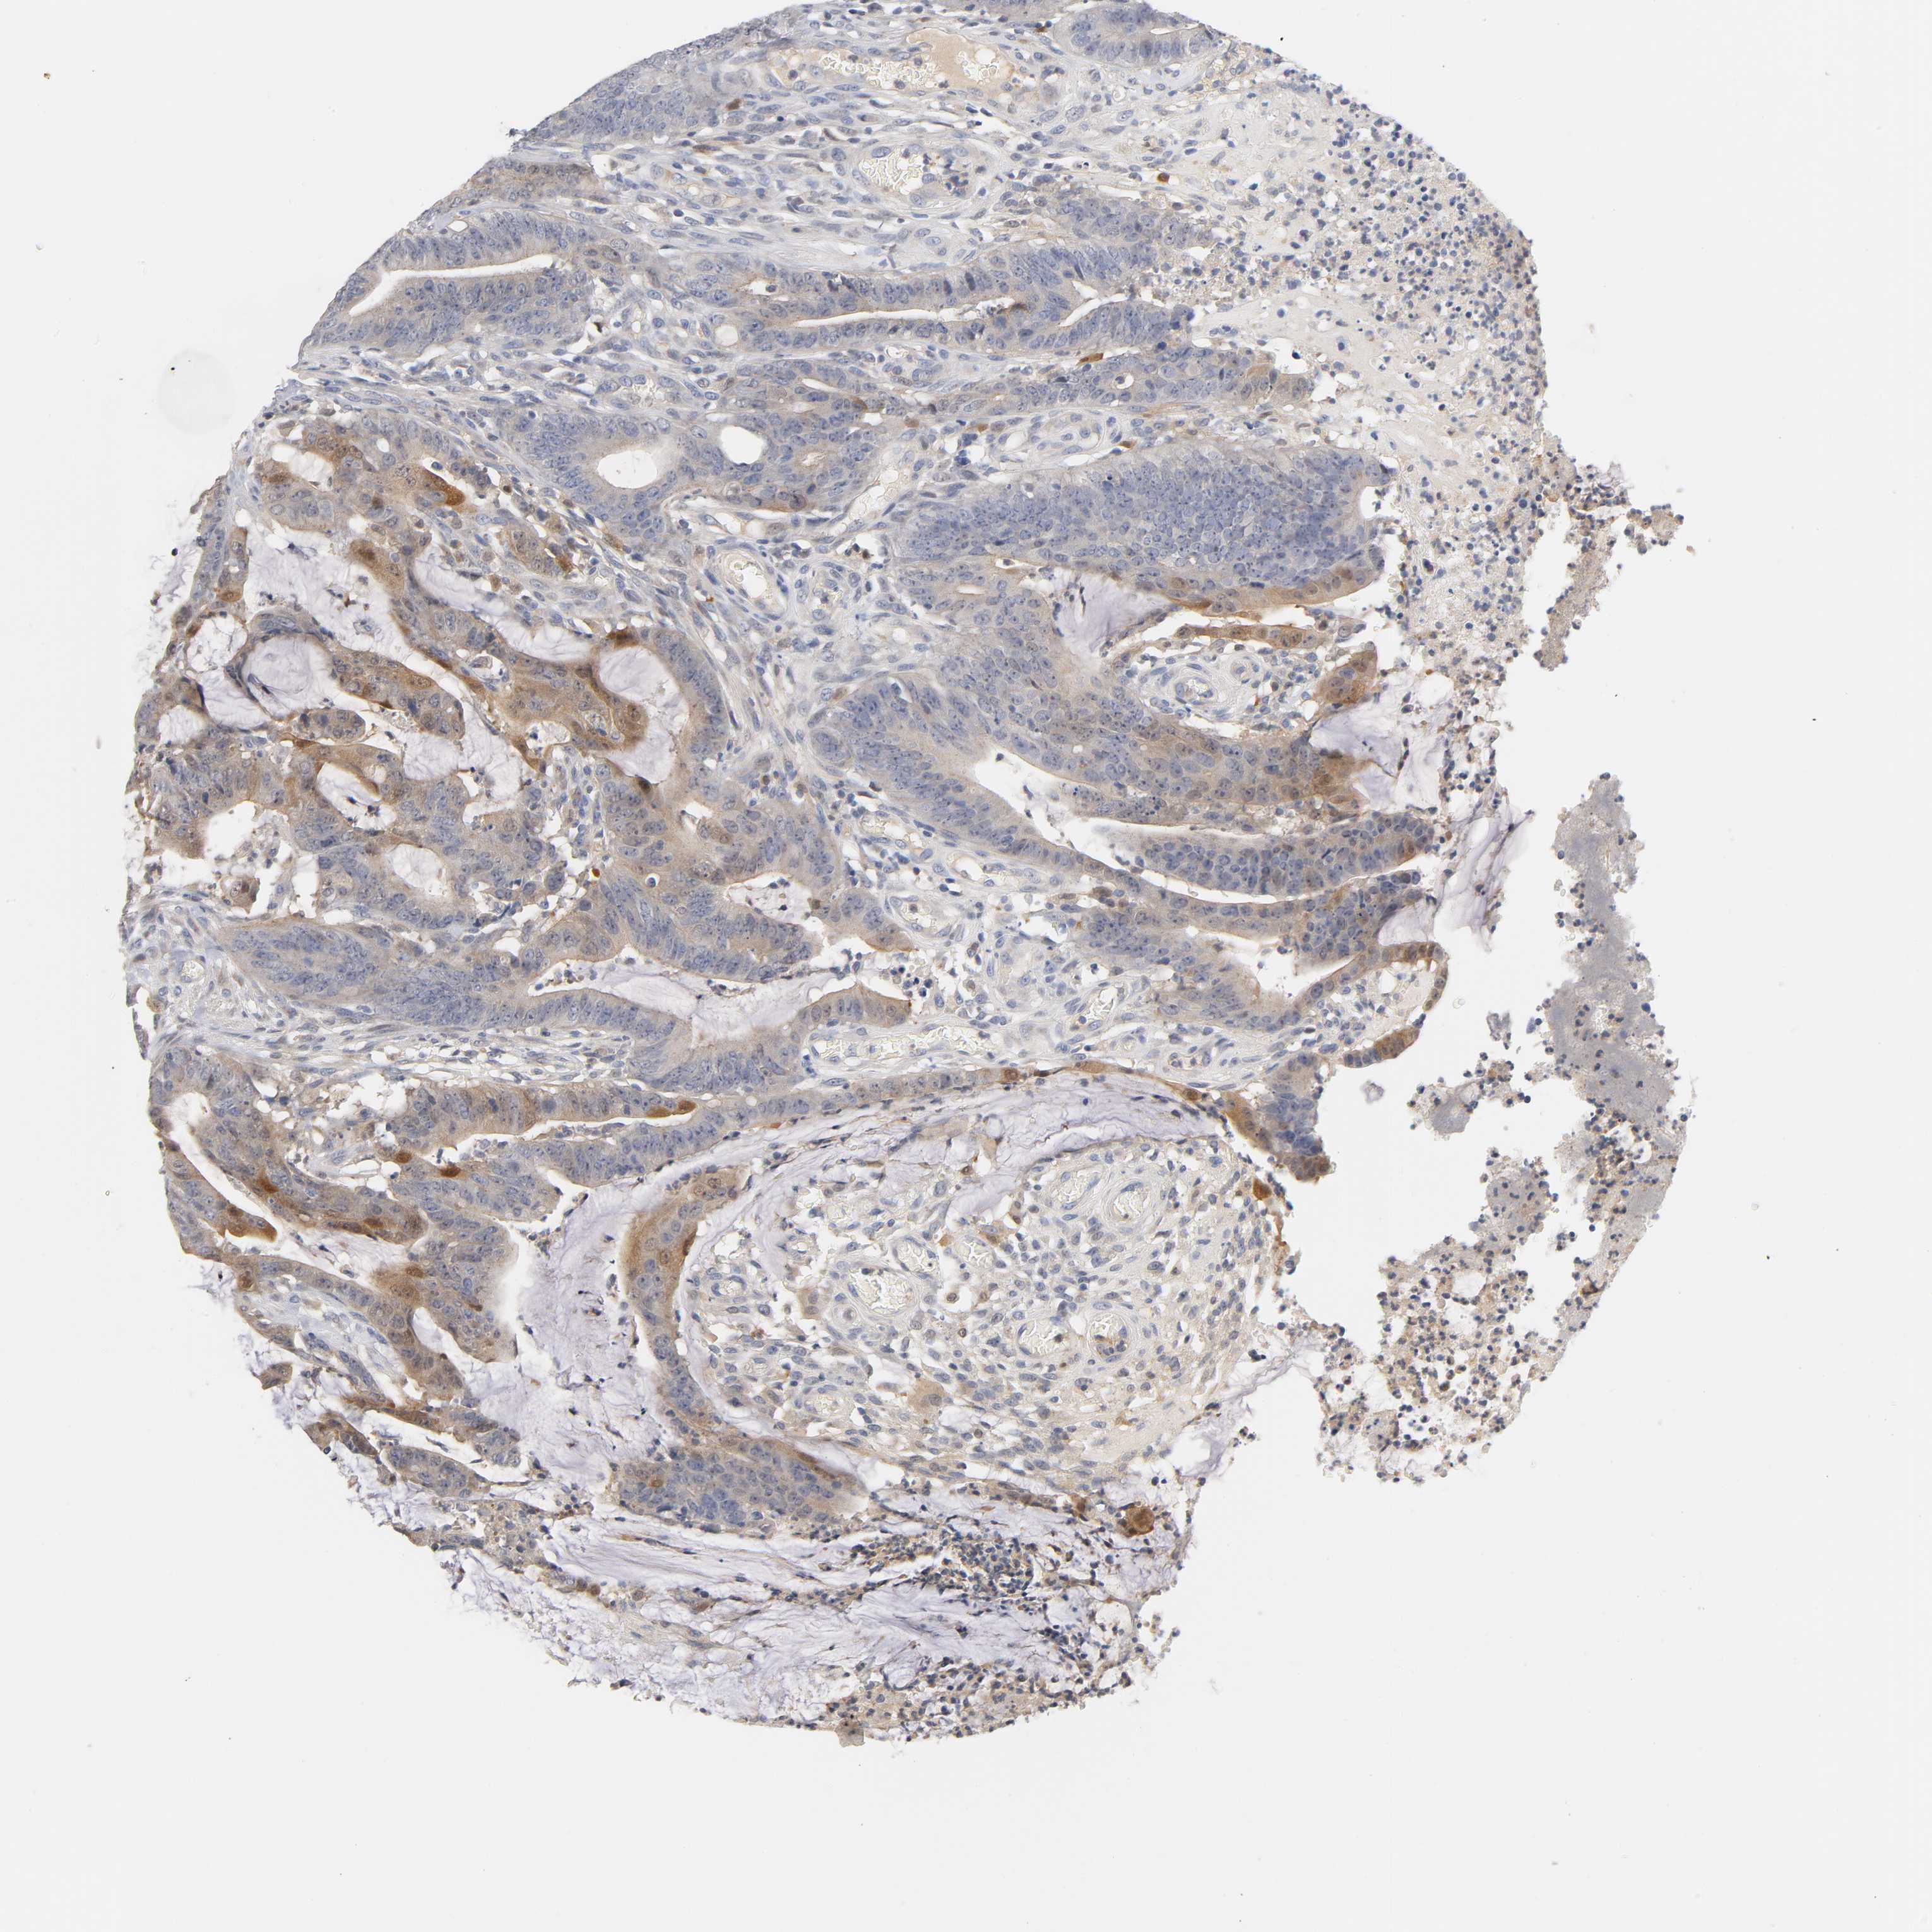

CANCER COLORECTAL CANCER Show tissue menu

Colorectal cancer

Human cancer